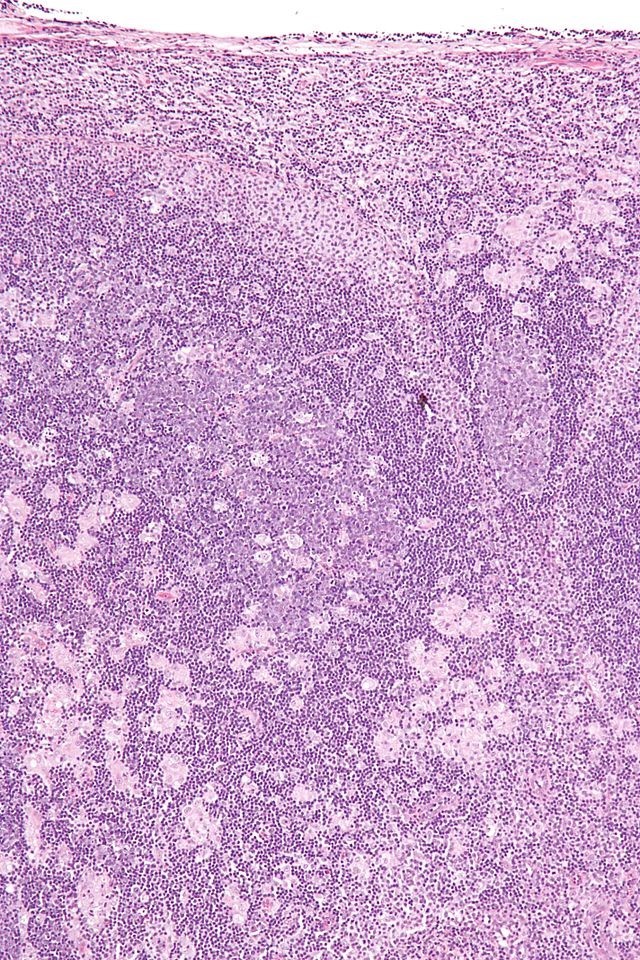

Diagnosis?

Marginal zone lymphoma

“monocytoid” lymps w/ abundant clear cytoplasm